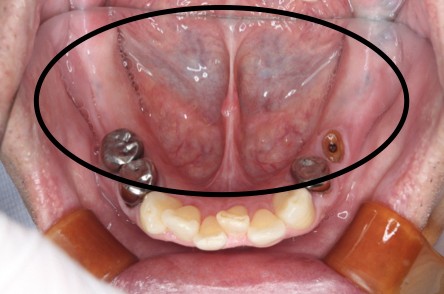

症例1

Before

After

主訴 | 奥歯で噛めるようになりたい |

|---|---|

治療内容 | 下顎の複数本の奥歯をインプラントにて再建 |

治療期間 | 6ヵ月 |

費用 | 200万円 |

副作用・リスク | ・術後に患部に腫れや痛み、違和感などが生じることがあります。 |